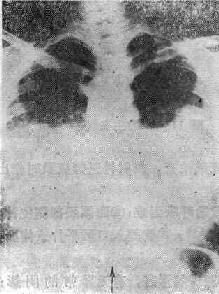

(一)中央型肺水肿 以两肺门为中心向两肺野扩展的阴影(可见支气管气影征),由深变淡,肺野边缘、肺尖肺底清晰,呈“蝶翼状”分布,这是中央型肺水肿典型的X线表现(图114-1)。常见于心脏和尿毒症患者。治疗及时一般很快吸收消失(3天之内);如治疗不及时,肺泡内除渗液外,可以为凝固的纤维蛋白巨噬细胞所充填。可产生炎性改变。肺水肿可继发感染

图114-1 心源性肺水肿的X线表现